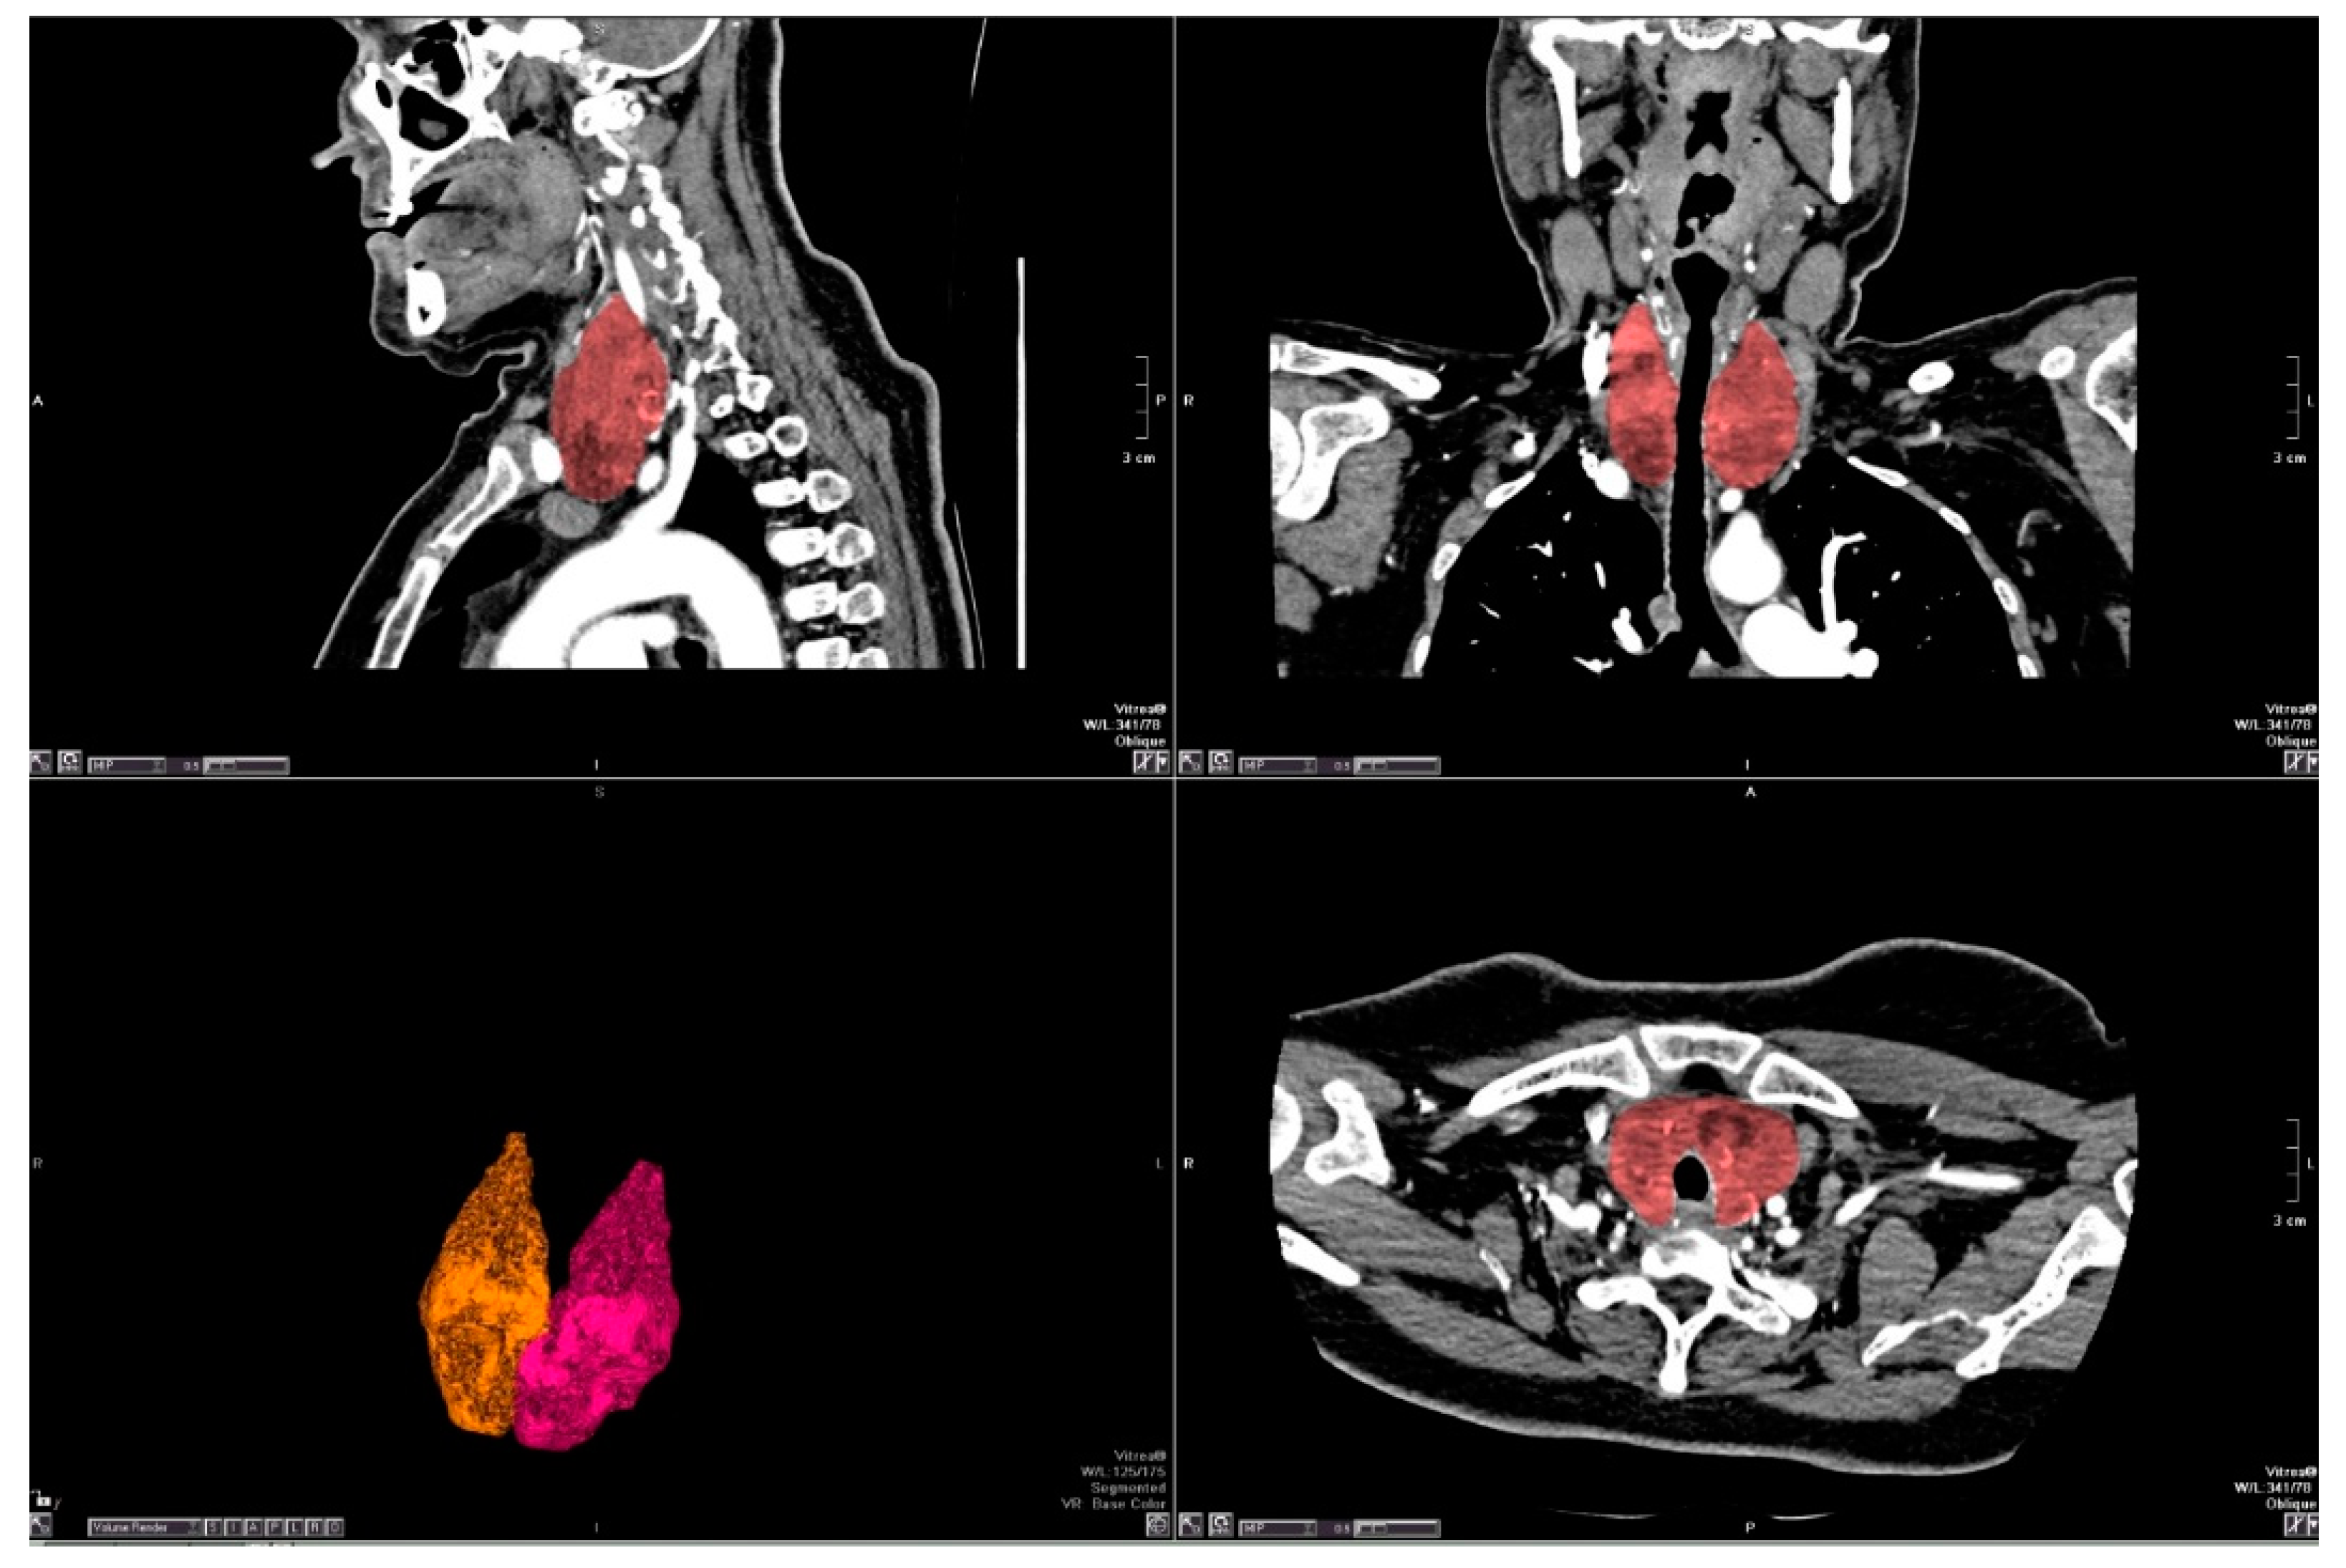

2.2. Radiological Analysis

2.2.2. Image Evaluation